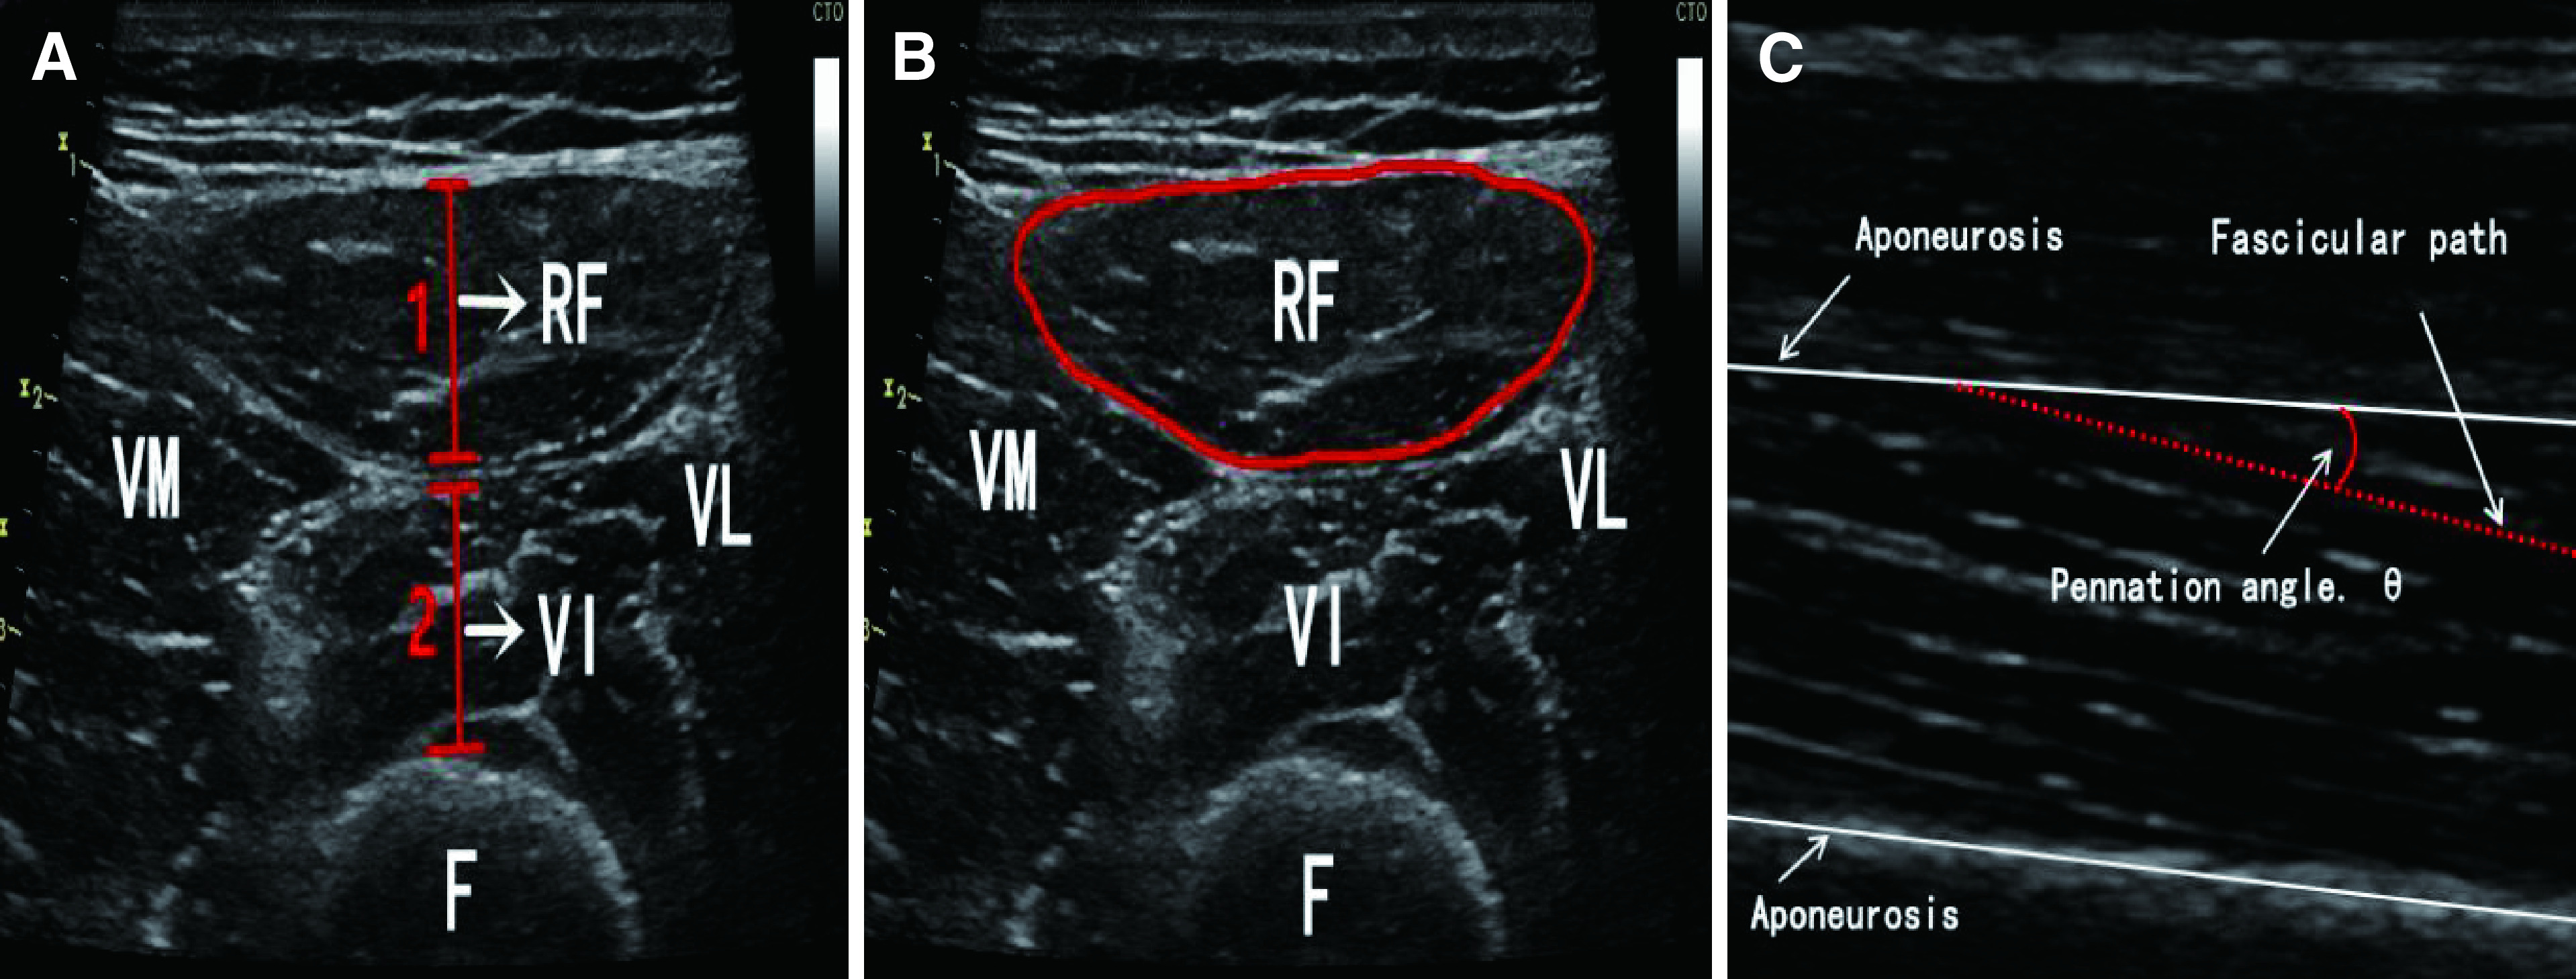

Methods: Baseline characteristics, preoperative laboratory data, and intra- and postoperative variables of 473 patients after CPB were determined in this prospective cohort study. Lower limb muscles on bedside ultrasound images were compared 1 day before and 7 days after CPB. Risk factors were assessed using logistic regression models.